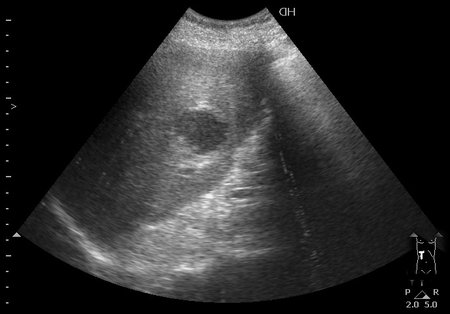

#3

08-09-04-134127_KRAYNOVA_20.jpg

Типичная картина ##1-4:

Гипоэхогенное неоднородное округлое образование, окруженное эхогенным "демаркационным валом"

измененной паренхимы печени.